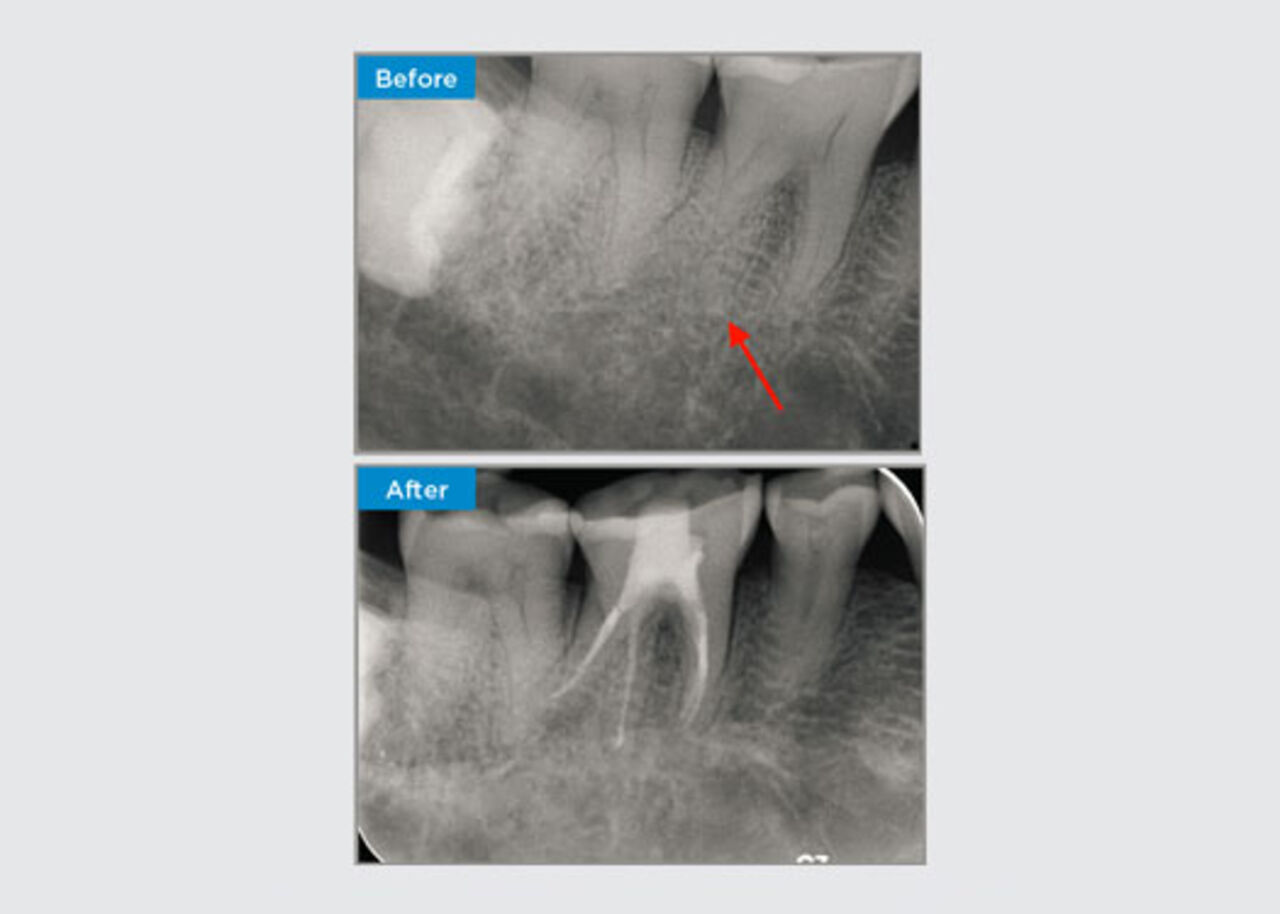

A 35 year old female patient presented after referral from a Specialist Periodontist. During the initial endodontic assessment the patient mentioned crown lengthening had been performed, prior to placement of the crown on tooth 16, two years earlier. Two months prior to the patient presenting, she had noted swelling of the palatal gingiva. The patient’s general dental practitioner had discovered a 7mm periodontal pocket adjacent the palatal sinus tract associated with tooth 16. The patient was referrred to a Specialist Periodontist. The Specialist Periodontist diagnosed a primary endodontic - secondary periodontal lesion. The patient had satisfactory oral hygiene and was a regular dental attender. Tooth 16 was tender to percussion. It was noted that the crown margins were satisfactory and the periodontal pockets around tooth 16 were less than 2mm deep on the buccal aspect, however on the palatal surface, adjacent the sinus tract there was a 6.5mm isolated periodontal pocket. Thermal testing of tooth 16 revealed a negative response. Tooth 16 had risk factors for apical periodontitis such as: a negative response to thermal testing, tenderness to percussion, a history of a deep restoration following crown lengthening surgery and radiographically identifiable periapical disease. Tooth 16 did not have a history of pain on biting or chewing, which may indicate a crack communicating with the pulp and/or periodontal tissues. The patient had no risk factors for periodontal disease and there was no abnormally deep pocketing present around any other teeth.

Dr Omar Ikram, Endodontist, Crows Nest, NSW Australia